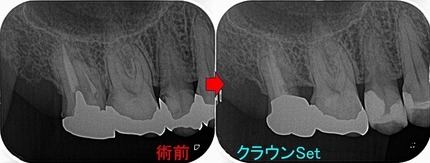

仮歯を入れて経過を見て行き

2026 EEdental SSY (5).jpg

ようやく1年、骨もしっかり戻ってきてくれています。

この後、クラウンは弱目の材料で作っていこうと計画しています。

悪くなった歯を保存させるのは難しい。。。(>。<)